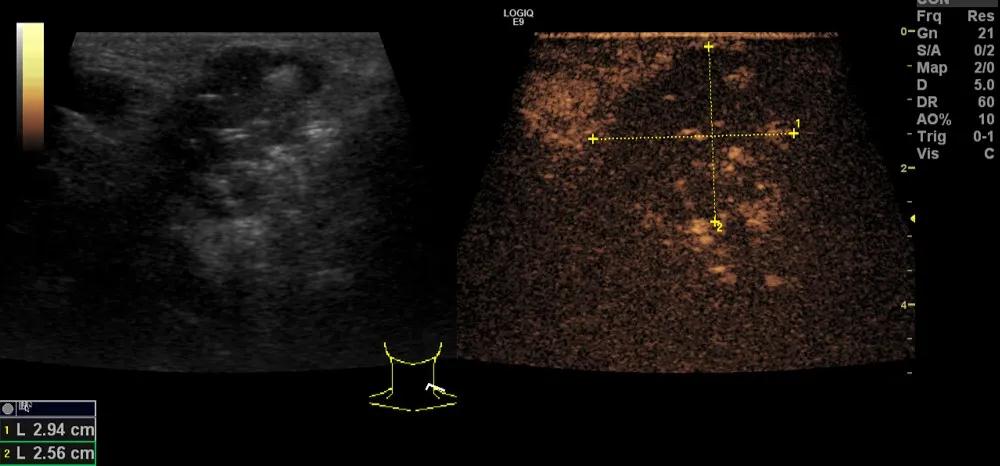

第二例是食管癌患者,术后半年余锁骨上固定淋巴结可触及肿大,疼痛非常明显,系统治疗后无缓解,患者希望通过局部处理缓解症状。造影显示强化信号明显,结节部分区域坏死,故主要针对强化区域从后向前的逐层的消融,皮下进行液体隔离减少烫伤。热消融后影像显示血流增强消失,弹性、硬度增高,一个月后复查显示充盈缺损,完全消融,疗效远超预期。

(病例2图例)